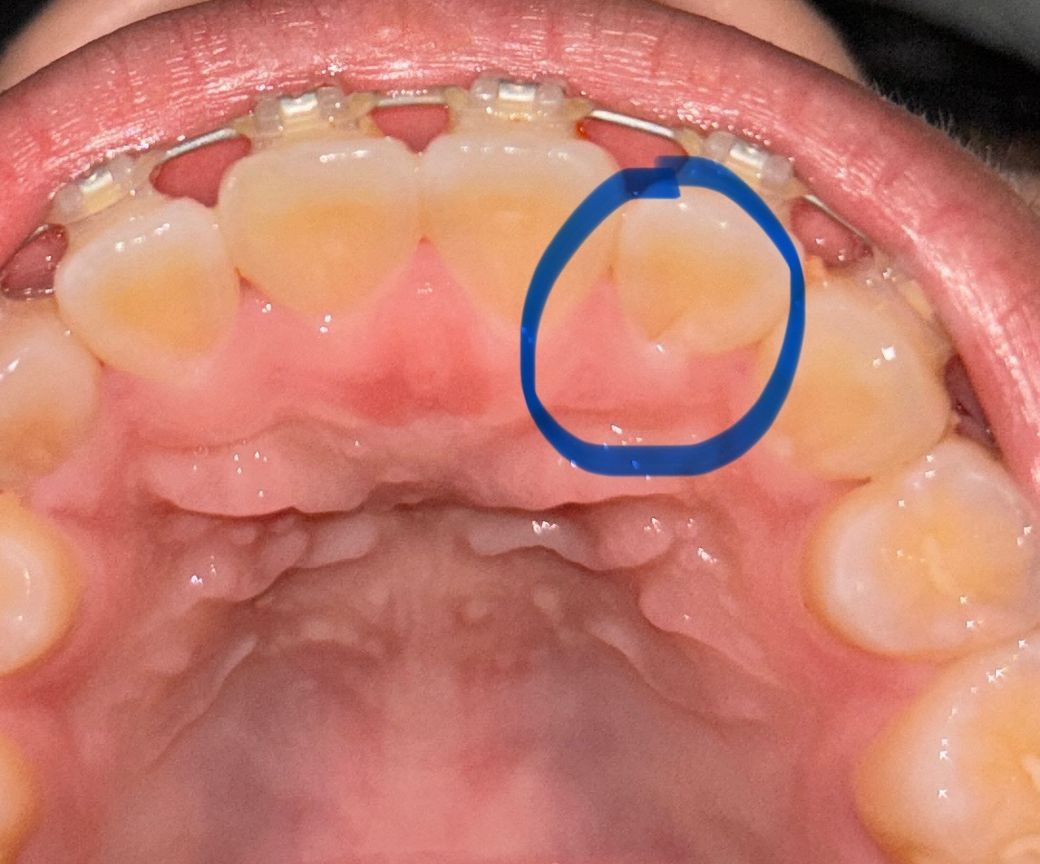

앞니 뒤쪽에 저런 선이 있는데 충치인가요 불과 2주전쯤 치과가서 충치이야기 할때는 앞니에 충치 잇다는 이야기는 못들엇는데.. 아프지듀 않습니다

네 충치입니다 충치가 잘 생기는 부위입니다 뒤쪽이라 주의깊게 보거나 특별히 충치가 있는지 점검해달라하지 않은 이상 못볼수도 있죠